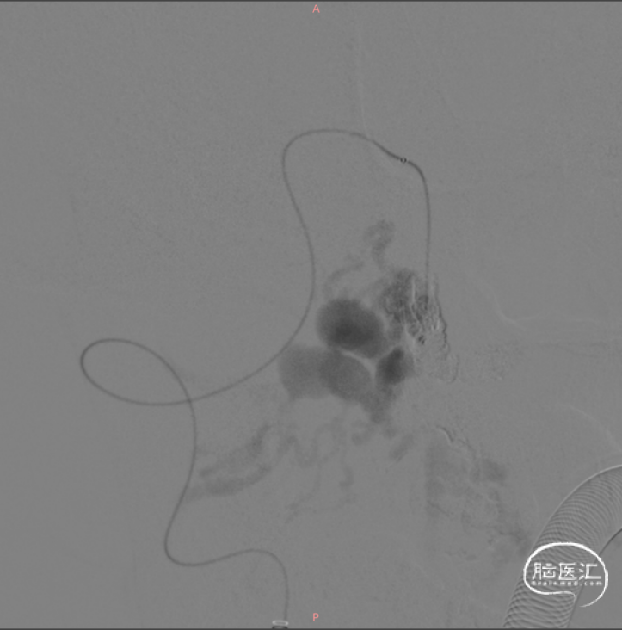

弹簧圈精准填塞瘘口

Onyx加固封堵瘘口

CCJ AVF完全不显影

右侧椎动脉造影CCJ AVF完全不显影,左侧PICA保护良好

2、虽然不少文献认为显微手术是治疗CCJ AVF首选的治疗方式,但是对于解剖部位难以暴露,血管条件满足导管到达瘘口的CCJ AVF,血管内介入治疗仍是一种有效的治疗方案。介入治疗的目标是闭塞瘘口,保持正常供应神经的血管,缓解静脉高压。本例案例供血侧的椎动脉由于上次手术封堵,缺乏良好通路,因此采用了对侧椎动脉“翻山”技术,将微导管超选至瘘口处。考虑到该病例瘘口较大,流量大,我们直接将弹簧圈在瘘口处以及左侧椎动脉的PICA近心端成篮的方式,限制栓塞材料过度弥散,精准封堵瘘口。

本病例的治疗难点集中于两点:其一,既往介入手术导致患侧椎动脉通路受阻,需另辟介入路径;其二,瘘口高血流量对栓塞材料稳定性提出极高要求。治疗团队应用对侧椎动脉“翻山”技术,成功建立逆向通路,突破解剖限制,展现了血管内介入操作的精准性与灵活性。针对瘘口高流量的挑战,术者采用弹簧圈于瘘口及左侧椎动脉PICA近心端“成篮式”填塞,这一策略巧妙平衡了瘘口完全闭塞与重要穿支血管保护的双重需求,体现了“精准栓塞”的核心治疗原则。